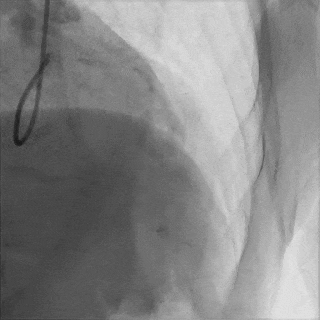

对角支送入IVUS导管,在IVUS实时指引下用尝试穿刺闭塞段

导丝未能进入闭塞段,导丝进入间隔支

逆向造影指引下继续尝试穿刺闭塞段

导丝远端与逆向造影不重叠,未在血管真腔

反复调整导丝最终进入D2#,可见导丝远端与D2侧枝重叠,证明远端位于真腔

微导管交换工作导丝至D2#远端

双腔微导管辅助下,导丝在逆向造影指引下成功通过LAD闭塞段,逆向造影显示导丝走行于LAD真腔内